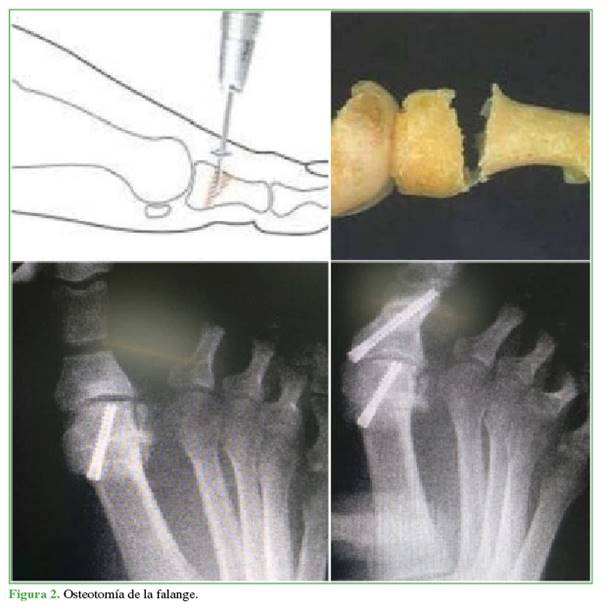

Osteotomía de la falange proximal. Se efectúa una incisión percutánea medial de 4 mm sobre la falange proximal a 1 cm distal de la articulación MTF, se procede a la desperiostización, la osteotomía en cuña dorsal con fresa tipo Shannon larga, al cierre por osteoclasia y se fija con tornillo de compresión, de proximal a distal y de medial a lateral, sin afectar la superficie articular de la falange (Figura 2).